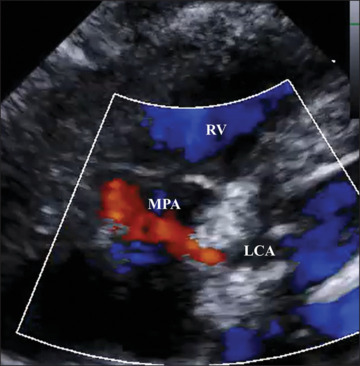

Imaging details of asymptomatic, nonischemic cases of anomalous left coronary artery from the pulmonary artery (ALCAPA) diagnosed in infancy are not well established. A 6-month-old girl was diagnosed with ALCAPA but showed normal left ventricular contraction. Echocardiography and coronary angiography revealed abundant collateral pathways from the right coronary artery to the left coronary artery (LCA), with the opening of the pulmonary artery narrowed to 1.5 mm and a restricted continuous flow from the LCA to the pulmonary artery. Coronary ostial stenosis could be one of the findings in asymptomatic, nonischemic ALCAPA.